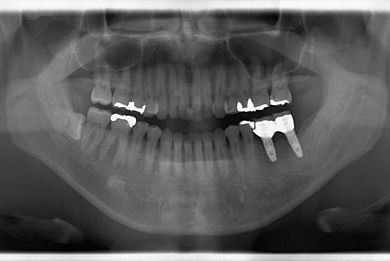

インプラントの症例写真 IMPLANT

インプラント治療

| 性別/年齢 | 男性 / 32歳 | ||||||||||||||||||||||||||||||||

| 主訴 | 銀歯がはずれたところの治療と、インプラント治療相談。 | ||||||||||||||||||||||||||||||||

| 治療方針 | 欠損部分をインプラント治療により、機能的・審美的回復を行う。 | ||||||||||||||||||||||||||||||||

| 治療内容 | インプラント2本、ハイブリッドセラミッククラウン2本 | ||||||||||||||||||||||||||||||||

| 総治療費 | 399,000円 | ||||||||||||||||||||||||||||||||

| 治療期間 | 7ヶ月 |